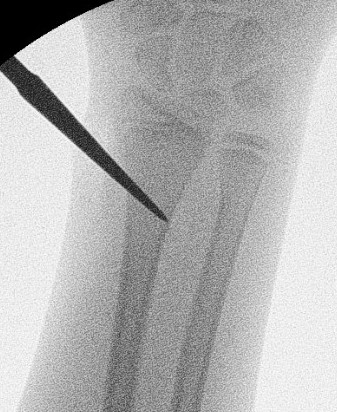

Manipulation under anaesthesia

Post reduction Positioning / Rule of Thirds

1. Fracture proximal to the insertion of Pronator Teres

Proximal fragment supinated by biceps

- supinate the forearm

- match proximal fragment

2. Fracture in the middle third

Midposition / neutral

- biceps / pronator teres balanced

3. Fracture in the distal third

Proximal fragment pronated by pronator teres

- pronation is the position of choice

1. MUA

Indications

- young patients < 10

- greenstick fractures